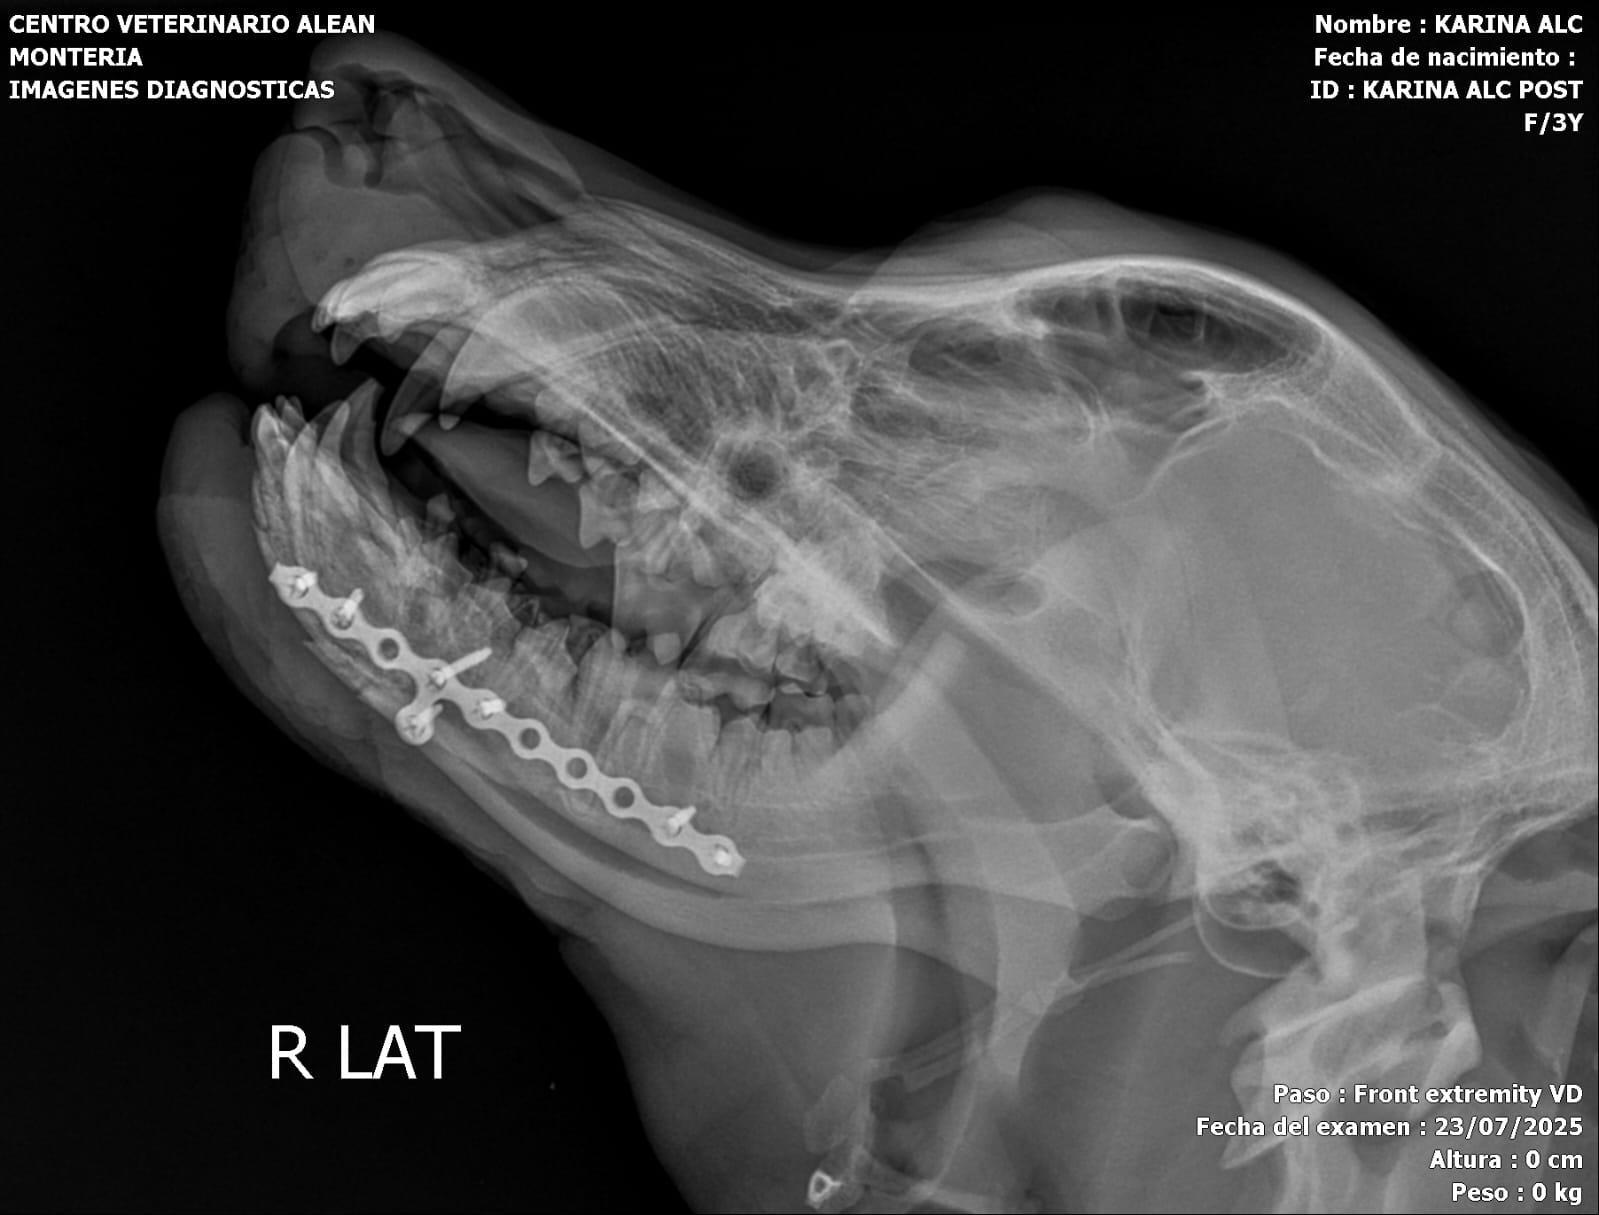

Hoy fue sometida a una tercera cirugía en la mandíbula, en la que se realizó una reconstrucción completa y una reducción total del radio. Además, se le colocó un sustituto óseo a base de silicofosfatos de sodio-calcio en el radio y la ulna.